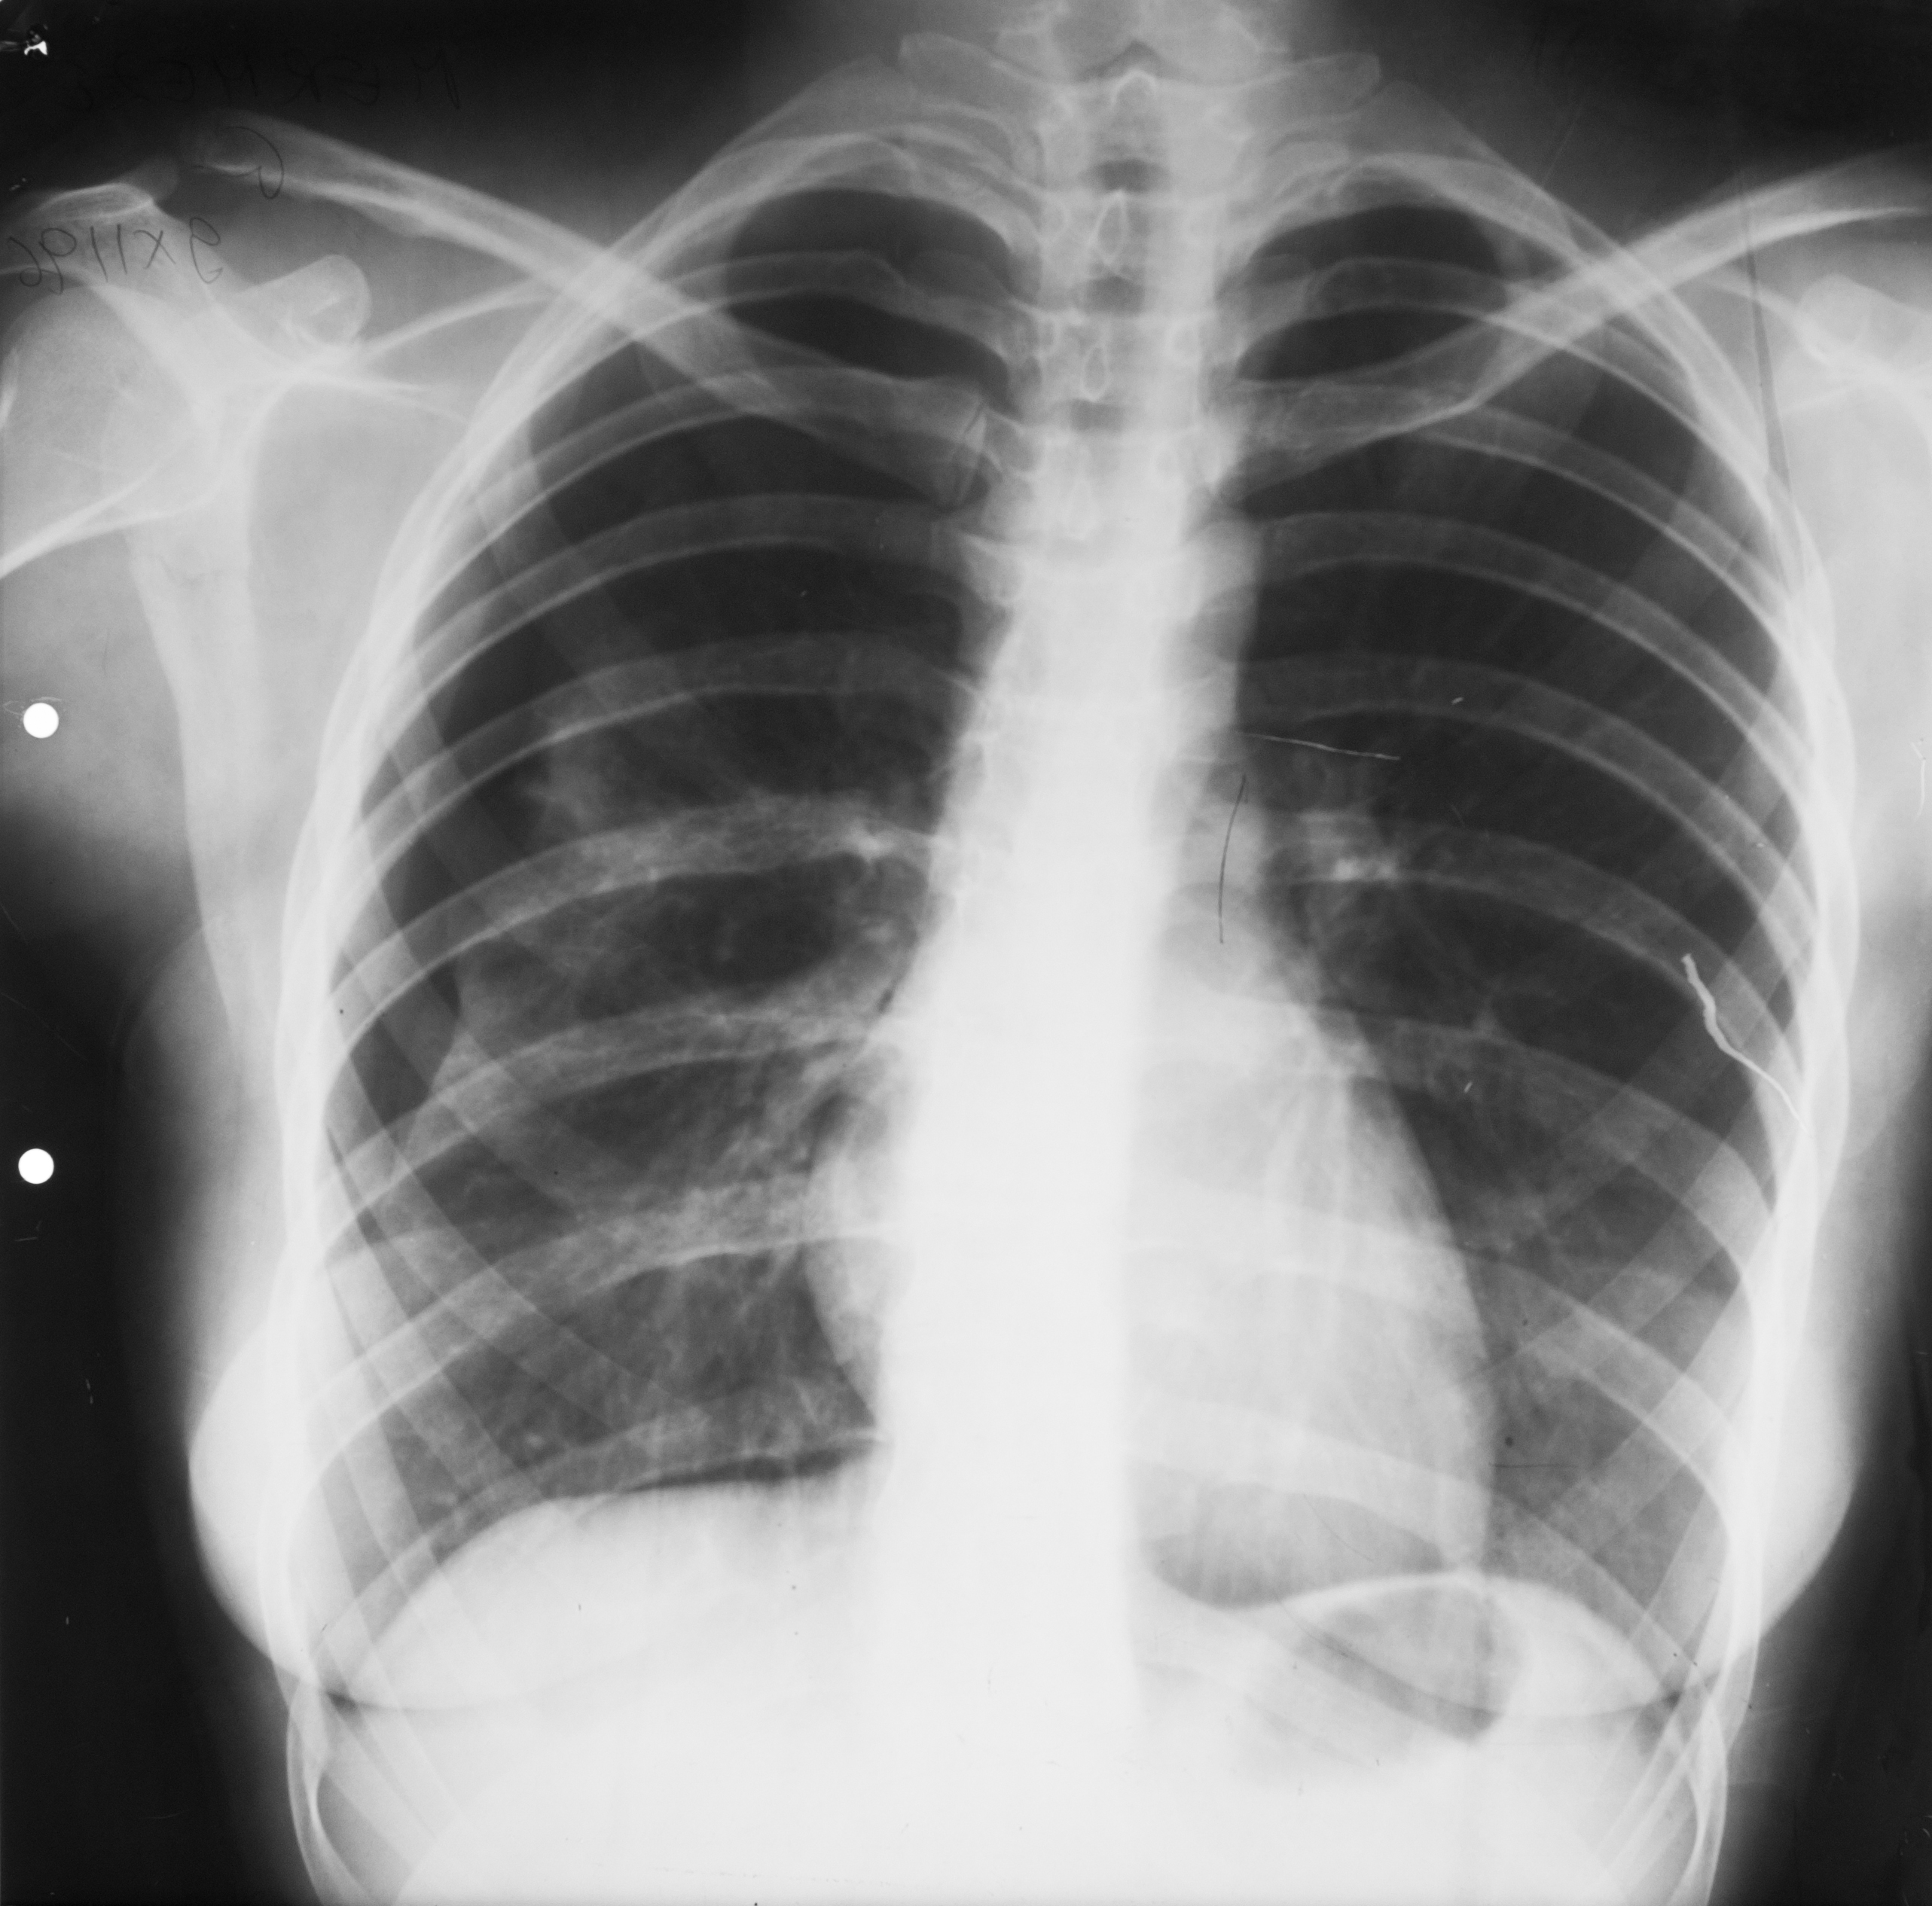

METASTAZE PULMONARE

Opacități bine,net liniar delimitate,având aproximativ aceeași intensitate,prezente în ambele câmpuri pulmonare(opacități=procese de condensare).

PNEUMONIE FRANCĂ LOBARĂ

Proces de condensare în jumătatea inferioară a câmpului pulmonar drept cu bronhogramă aerică ce vine în contact cu cordul

PNEUMONIE FRANCĂ LOBARĂ

Condensare cu bronhogramă aerică ce ocupă un lob întreg